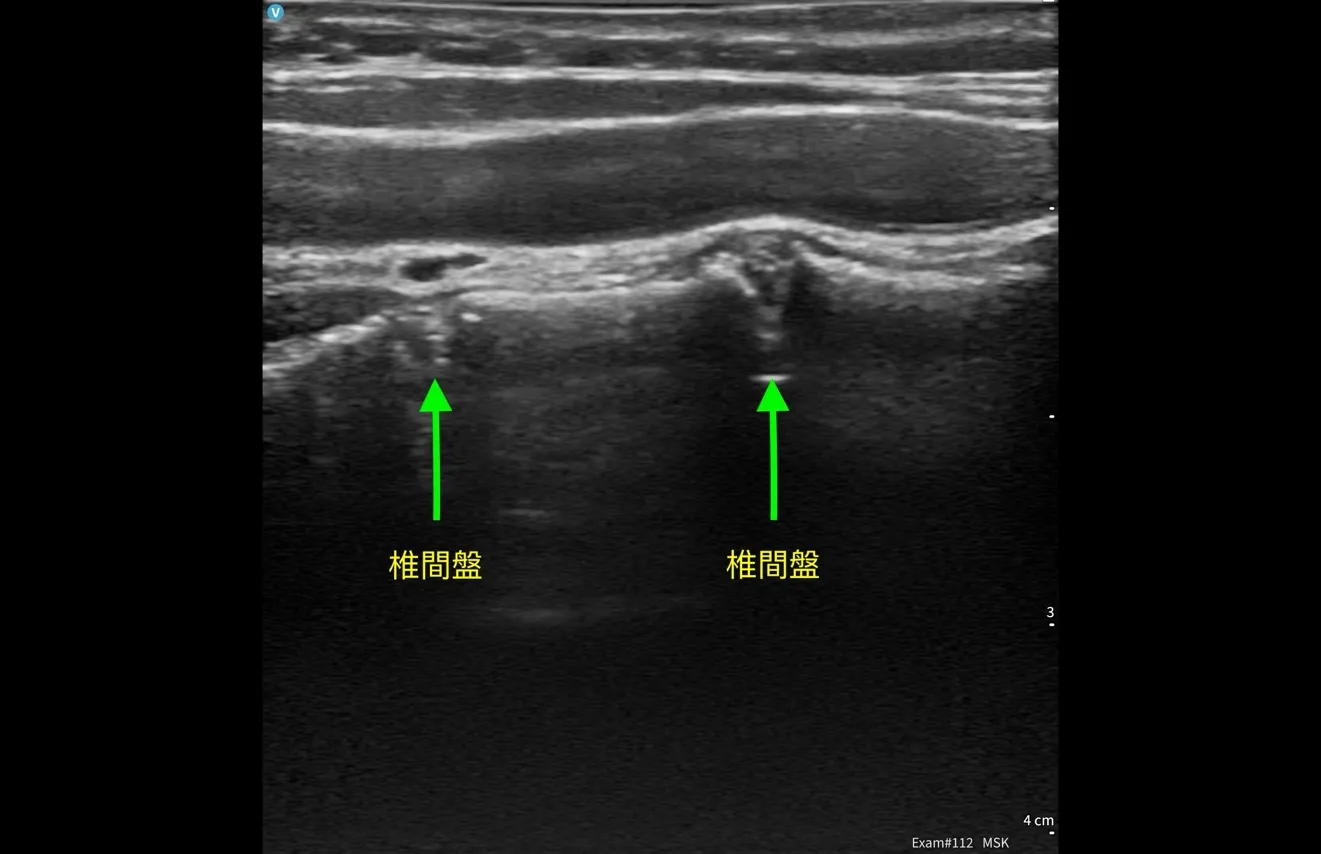

我使用超音波由頸部前外側向後檢查椎間盤健康狀態,看到 C5/6/7 段椎間盤變扁,並伴隨小鈣化訊號。 再往頸部側邊掃描,在神經根出口附近,探頭輕壓就能誘發她熟悉的痠痛與痠麻。 同時在頸部後側椎旁肌群,與健側比較,下段也呈現明顯纖維化與脂肪浸潤樣態。

這些發現讓我判斷:除了椎間盤本身,神經根出口周邊的高張力與沾黏軟組織很可能是讓症狀被持續放大的關鍵。

- 超音波線索:C5/6/7 段退變相關訊號;神經根出口附近輕壓可誘發熟悉痠麻;下段椎旁肌結構改變(纖維化/脂肪浸潤樣態)。